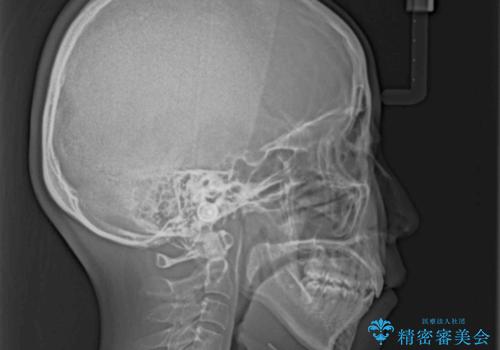

上下顎ともに前突しており、特に上顎は著しい突出感でした。

また、下顎歯列には左右差があり、非対称な抜歯が必要と判断されたため、治療は困難なものとなりました。

それでも根気強く通院してくださり、横からの顔貌の印象が大きく改善され、スムーズに口が閉じられるようになりました。